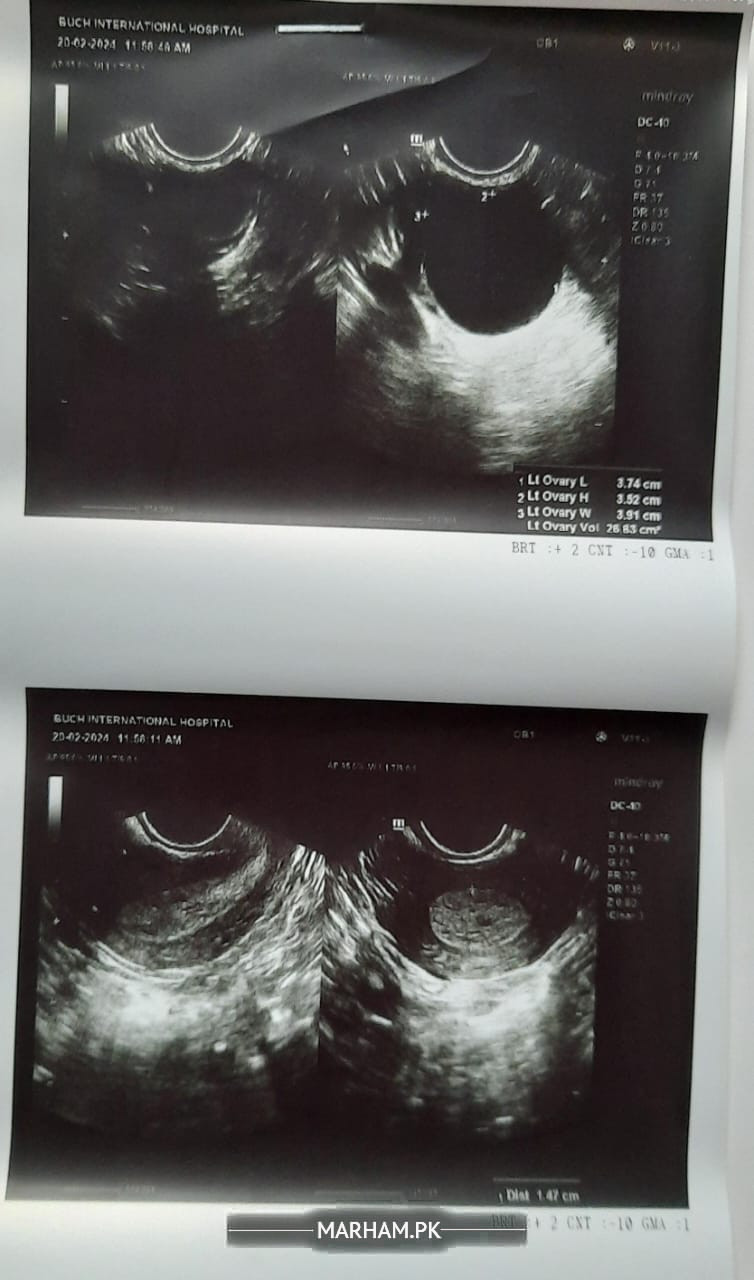

Aoa mj dates ka issue tha irregular thi spotting th blkl light 2 din bs bleeding hoi thri c os k baed phr spotting doc ko dkhya osny Kaha k Duphaston 7 din subha dophr sham ln or cyst h ovary m osky lye danzen tablet d or kaha k 7 din Duphaston lainy k baed apko bleeding ho g os k baed checkup k lye ayn per aj 9 din hai duphaston chorhy hoe pr bleeding nh h bs aj phr esy blkl light spotting h brown discharge h clot type.. Bleeding nh hai kindly sir guide krn kia kru dobra doc k pass jau w8 kru bleeding ka

Scan

ultrasound report? blood tests?